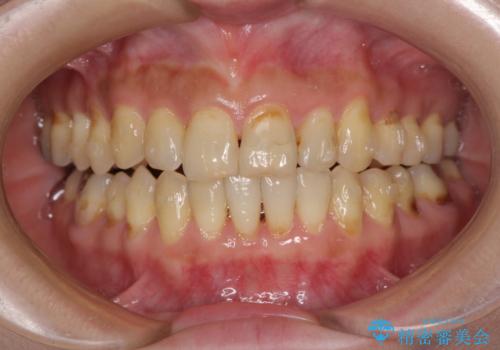

- 歯列不正と、どこで咬んで良いのか分からない咬み合わせを気にして来院された患者様です。

下顎骨は左側にシフトしており、咬み合ったときには奥歯と前歯の一部しか接触していない状態でした。

骨格的な左右差は歯列矯正は改善できないため、上下歯列が全体的に接触することをゴールとしてインビザラインにて矯正治療を行うこととしました。